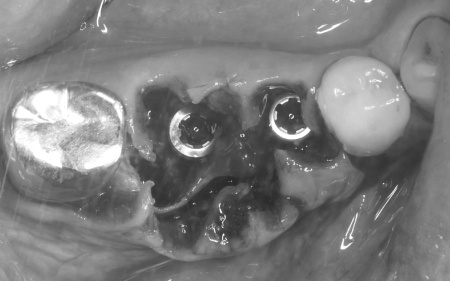

歯根破折が疑われました。

抜歯後の骨の状態を確認しています。

治療中

インプラント体と骨の結合を確認しました。